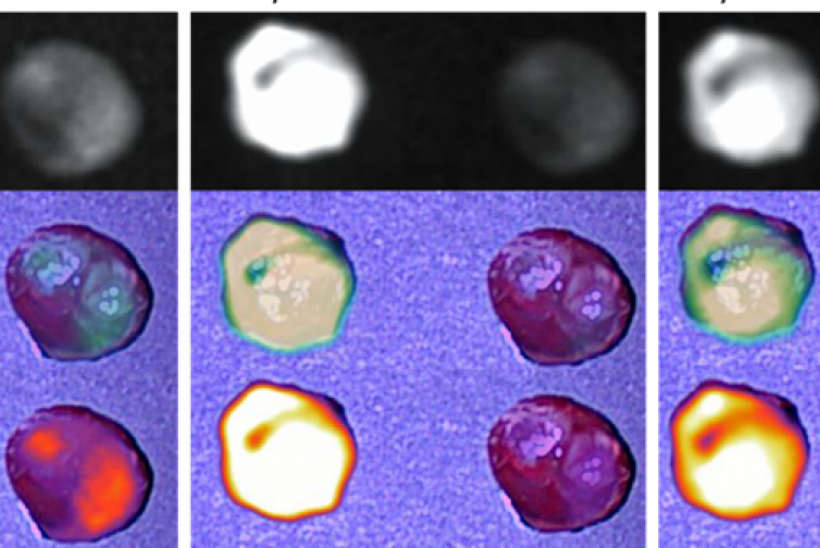

The fluorophores will be attached to antibodies that specifically target a protein present on the membrane of cancer cells and injected intravenously before an operation. Following, a custom-designed camera will be used to help surgeons visualize the 'glowing' cancer margins.

1. Tumour visualisation: By ‘lighting up’ tumours, surgeons will be able find the cancer more easily and remove it, avoiding vital organs like the kidney and liver.

2. Removal of residual cancer: After the cancer has been located and mostly removed, the surgeons can use an innovative scanner to look for small pieces of the tumour that are left behind. These will be visible as ‘glowing’ spots under the camera.

A specially designed camera set-up allow surgeons to find the tumours in mice.